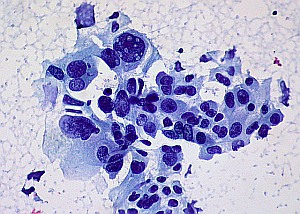

Krebszellen: Genom könnte Schätze enthalten (Foto: Flickr/Uthman) |